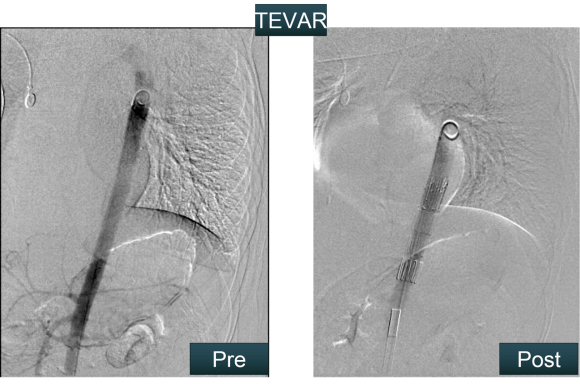

This has several advantages over conduit creation which can be a morbid and high risk procedure in patients who require minimally invasive approach. A graft is avoided. The artery is over 8mm in diameter where with stenting up to 8mm with an occlusive plaque, the danger of rupture is present, and often ballooning is restricted to 6mm-7mm. This is insufficient for many TEVAR grafts and TAVR valves.